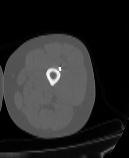

Бедренная кость является наиболее крупной трубчатой костью скелета человека и выполняет основную опорную функцию, обеспечивая прямохождение человека. Головка бедренной кости соединяется с вертлужной впадиной костей таза, образуя тазобедренный сустав, обеспечивающий движения нижней конечности.

КТ предусматривает использование рентгеновского излучения, которое хорошо поглощается костной тканью. В результате сканирования и последующей цифровой обработки полученных данных получаются подробные снимки в различных плоскостях, а также трехмерные изображения бедренной кости и тазобедренных суставов, которые можно увеличить и повернуть в разные стороны.

Снимки высокого разрешения позволяют выявить минимальные изменения в костных структурах и окружающих тканях. Мультиспиральная КТ может применяться в экстренных ситуациях для диагностики травматических повреждений бедренной кости и тазобедренных суставов, в частности, при переломах шейки бедра. Кроме того, исследование незаменимо при планировании оперативного вмешательства, а также в послеоперационном периоде для оценки успешности проведенной операции и для отслеживания процесса восстановления.

КТ бедренной кости помогает выявить воспалительные изменения, очаги деструкции костной ткани, доброкачественные и злокачественные новообразования. При подозрении на опухолевый процесс дополнительно применяется контрастное усиление. Для этого пациенту внутривенно вводится контрастный препарат на основе йода, который в большей степени, чем окружающие ткани, поглощает рентгеновские лучи. Поэтому при попадании в опухолевые очаги он обеспечивает их яркую визуализацию на снимках КТ. Методика контрастирования помогает обнаружить опухоли минимальных размеров, определить точные границы опухолевого очага, степень его прорастания в окружающие ткани, эта информация необходима врачу для назначения эффективной тактики лечения.